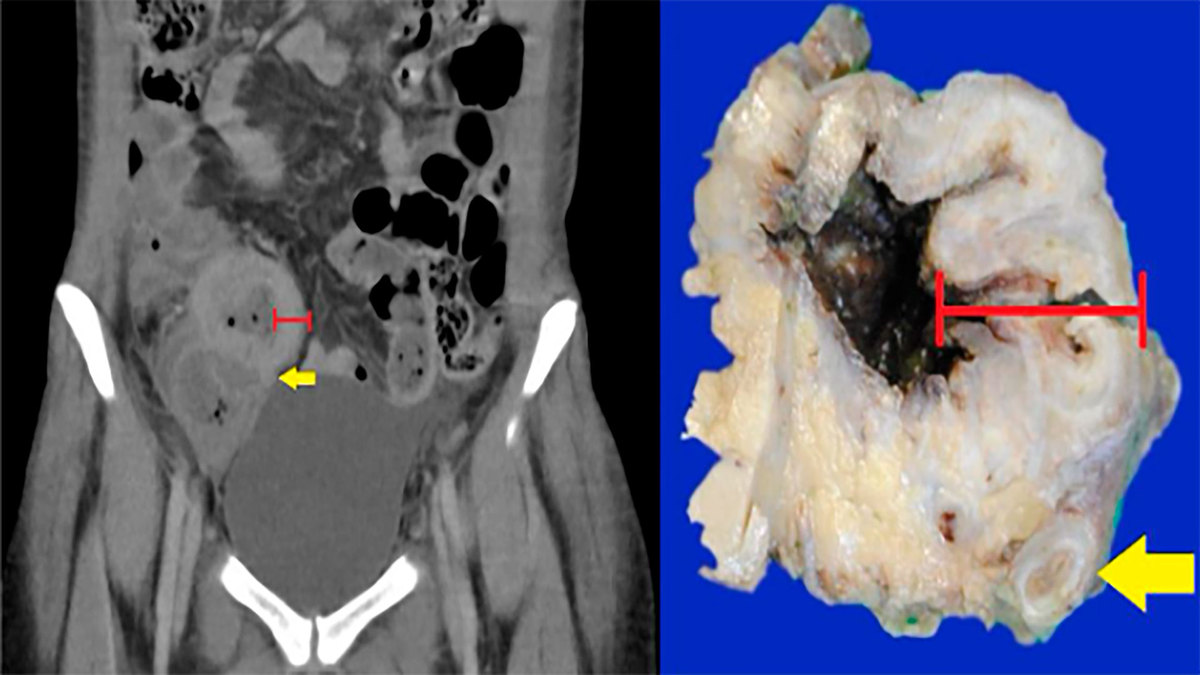

Em casos de suspeita clínica, o exame de imagem de escolha é a tomografia computadorizada de abdome. Os principais achados são: espessamento circunferencial e assimétrico de segmentos intestinais (podendo ter áreas de estenose – Sinal de Stierlin), linfonodomegalia abundante com centro liquefeito ou necrótico (necrose caseosa), sinais inflamatórios em planos gordurosos adjacentes.

A biópsia, que pode ser feita por meio de colonoscopia, é utilizada para o diagnóstico definitivo. Macroscopicamente, pode se apresentar de forma ulcerativa, hipertrófica ou um combinado dos dois. Na forma ulcerativa, há múltiplas úlceras, superficiais e profundas e circunferenciais. Na forma hipertrófica, predomina espessamento parietal e aparência de massa. Essas lesões sofrem fibrose, resultando em cicatrizes e áreas de estenose luminal.

Microscopicamente, é visto granulomas caseosos, frequentemente numerosos e confluentes, com periferia contendo uma mistura de linfócitos, plasmócitos e células gigantes. A pesquisa de bacilos-ácidos resistentes (BAAR) permite encontrar o agente etiológico nas áreas de necrose e granuloma.